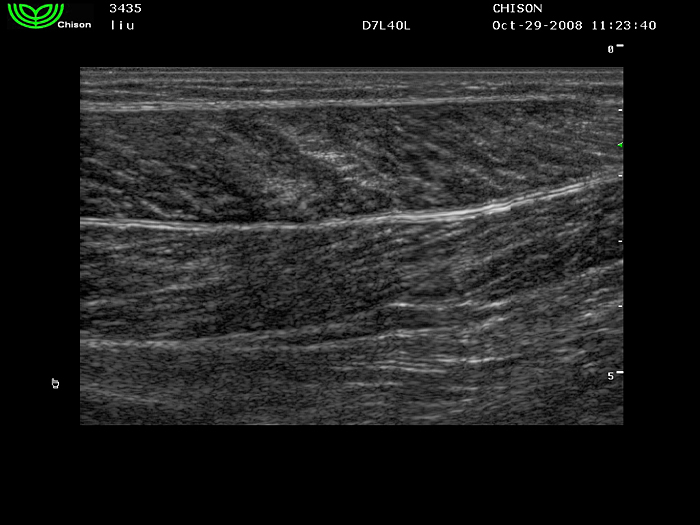

D7L40L 7.5МГц, линейный.

4.0МГц – 13.0 МГц. Применения: грудь, малые органы, нервы, сосуды, венозная катетеризация, мышцы и скелет, управление биопсией. |